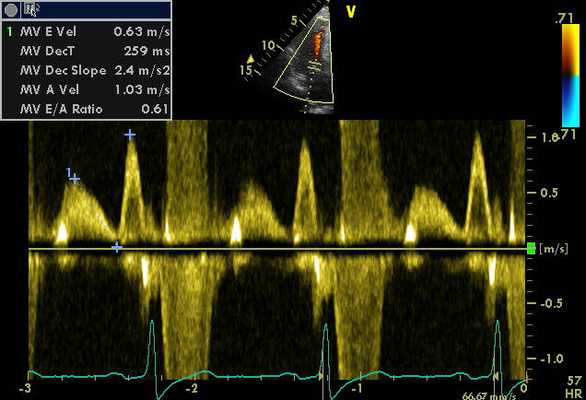

Миокардиальный рабочий индекс (МРИ) - один из наиболее информативных показателей «глобальной» сократимости миокарда [1, 2]. Он описан A. Stoylen и соавт. как «. индекс суммарной работы миокарда (MRI)» и рассчитывается методом допплер-эхокардиографии (Д-ЭхоКГ) по графику допплеровского спектра трансмитрального потока: MRI = (ИВС+ИВР)/ПИКлж, где (ИВС+ИВР) - суммарное изометрическое состояние миокарда, ПИКлж - период изгнания крови из ЛЖ [3]. Этот индекс по сути характеризует соотношение потенциальной (суммарное изометрическое состояние) и кинетической (период динамического изгнания крови из ЛЖ) энергии миокарда ЛЖ. Использование данного индекса ограничено при правожелудочковой дисфункции у больных с сопутствующей легочной патологией и с легочной гипертензией.

В 1995 г. С. Tei и соавт. [4] впервые предложили рассчитывать МРИ (Tei индекс) по допплеровскому спектру трансмитрального и трансаортального потоков при Д-ЭхоКГ. Представляются важными изучение и сравнение значений МРИ, полученных в режиме импульсно-волновой тканевой допплерографии (ТД) и при постобработке тканевого допплеровского изображения (ТДИ).

Методика импульсно-волновой ТД

Анализ продольного движения миокарда проводился в верхушечном 4-камерном срезе сердца с синхронной записью мониторного отведения ЭКГ при задержке дыхания пациента в течение 5-10 сердечных циклов (рис. 1). Контрольный объем (5x8 мм) ТД размещался в латеральной и медиальной частях фиброзного кольца митрального клапана (МФК). Точкой начала отсчета временных фаз считали зубец R ЭКГ. Проводился анализ параметров ТД от латеральной (МФКл) и медиальной (МФКм) частей фиброзного кольца митрального клапана: ТМРИ вычислялся по ТД в медиальной и латеральной частях МФК по графикам максимальной скорости движения МФК как отношение разницы временного интервала между началом положительной волны ИВС до начала «Еm» (a’) и временем систолической волны Sm (b’), по формуле:

![Принцип расчета ТМРИ по ТД фиброзного кольца митрального клапана]()

Рис. 1. Принцип расчета ТМРИ по ТД фиброзного кольца митрального клапана.